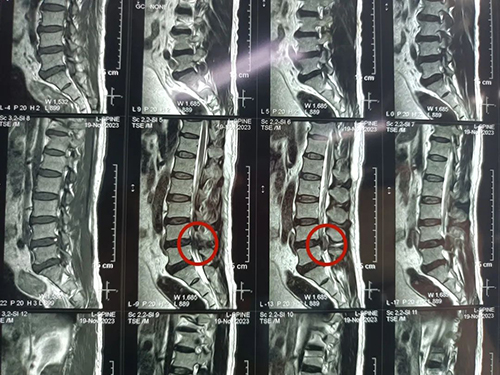

术前

我院骨科团队第一时间了解患者情况,为其安排各项检查。邹先生被确诊为:L4、5椎间盘突出症(游离型),马尾神经综合征。患者大小便功能障碍已经5天,且症状逐渐加重,情况较为紧急,于是骨科团队为邹先生在急诊全麻下行:L4/5椎间盘脱出症腰后入路+L4、L5椎体钉棒内固定+全椎板切除术+椎管扩大减压神经根松解+椎间植骨融合器融合术,手术顺利,术中成功固定L4、L5椎体钉棒,并摘除卡压神经根处的髓核组织。